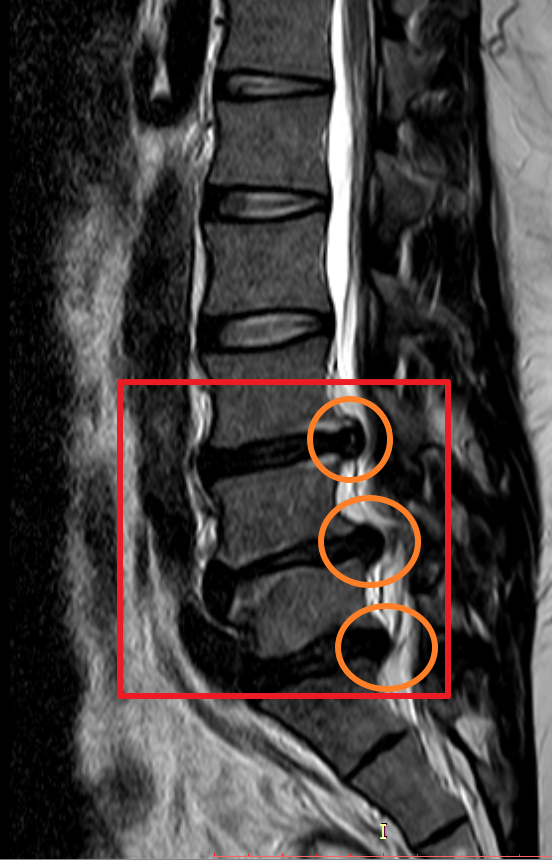

마지막으로 제가 촬영했었던 MRI 촬영 이미지를 첨부해 볼까 합니다. 이미지 순서대로 2014년, 2018년, 2020년 촬영했던 MRI 사진입니다. MRI 촬영 당시 허리디스크 상태가 좋지 않은 상황에서만 세 차례 찍었던 것이기에 이점도 고려해서 참고하시면 좋을 듯합니다.

이미지를 보시면 빨간색 네모 칸에 하얀색 기다란 세로 라인이 신경이 지나가는 부분이며 가장 바깥쪽 두꺼운 흰색 부분은 배 쪽의 지방입니다.

2014년 당시 대체로 튀어나온 허리디스크는 없으나 주황색 동그라미 부분에 엄청나게 많이 신경을 누르고 있었던 상황

2018년 첫번째 허리 디스크가 첫번째 디스크가 여전히 눌려져 있으며 추가로 두번쨰 디스크가 신경을 많이 누르고 있으며 세번째 디스크는 조금씩 나오는 상황.